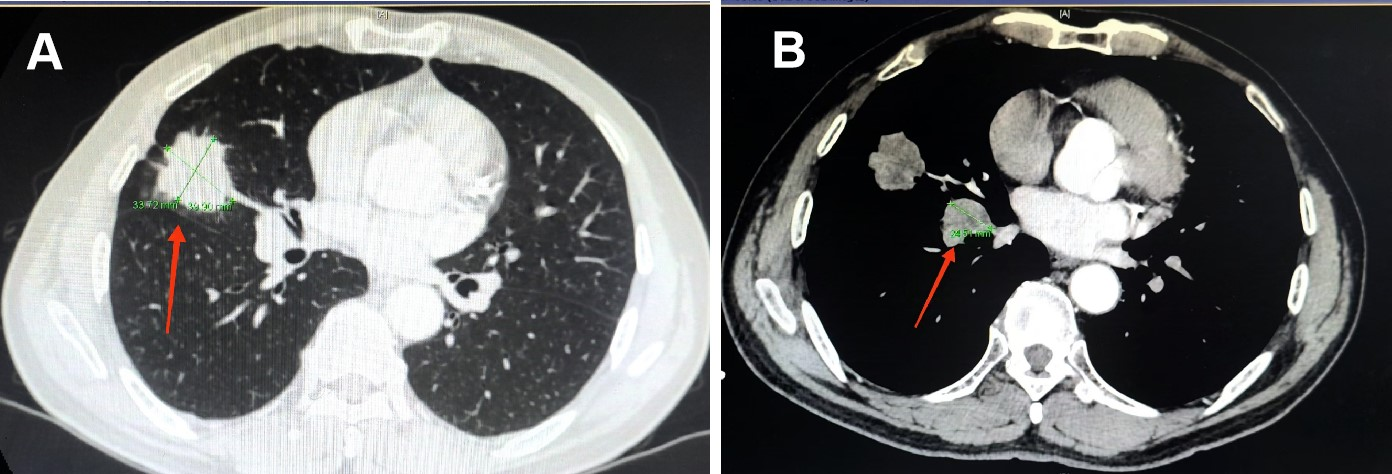

今年5月,合川72岁的向先生体检时发现右肺长了一个近4cm大小的包块(见图2),为明确诊断他慕名来到新桥医院呼吸与危重症医学中心门诊。通过入院后病理活检和系统检查,确诊为右肺小细胞肺癌 T2aN2M0 IIIA期。针对向先生的病情,呼吸与危重症医学中心主任徐智教授高度重视,组织团队进行病情讨论。大家一致认为,早期(IA-IIA期)小细胞肺癌最佳治方案是手术治疗,而晚期小细胞肺癌则适宜采用化疗联合免疫治疗。对于向先生这样介于早晚期之间的IIB-IIIB病人,大多数只能按照传统方案进行化疗联合放疗,治疗后复发和转移风险较高。

图2 向先生治疗前的CT,原发肿瘤近4cm(见图A红色箭头)和肺门转移淋巴结(见图B红色箭头)